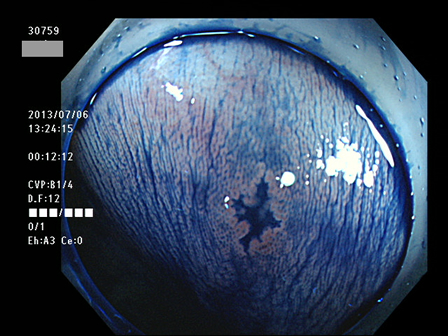

上記100名より抽出した平坦・陥凹型腺腫(=癌化の危険が高いが見落としやすい病変)の内視鏡写真